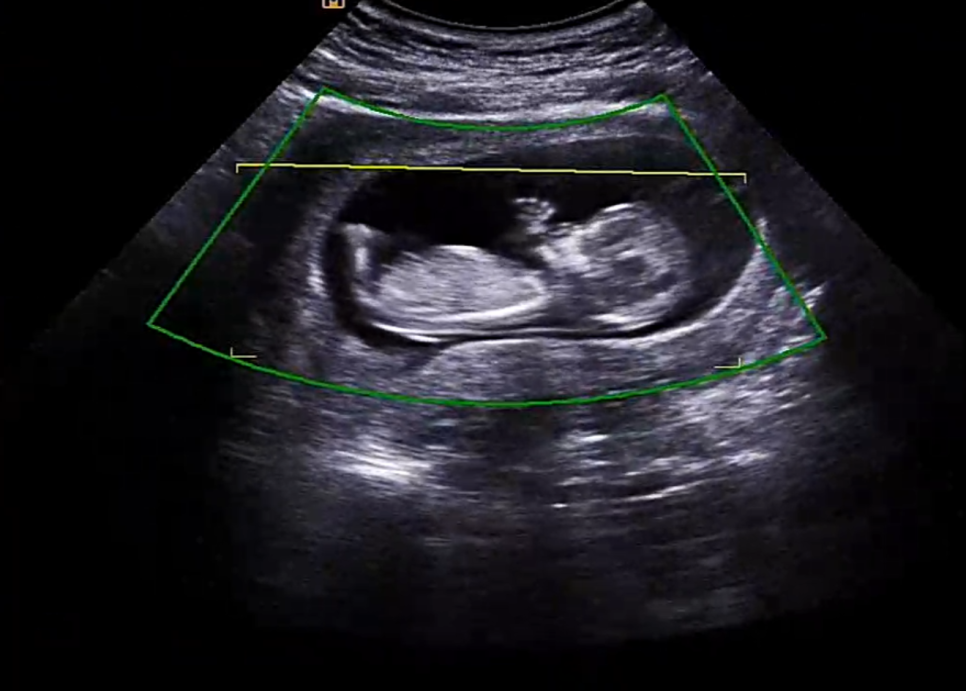

검사 중 발차기 실력을 자랑하는 오토야

우선 1차기형아검사 초음파에서 제일 먼저 확인했던 머리~꼬리뼈의 길이 ㅎㅎ #임신 12주차 정도가 되면 6~7cm 정도가 된다고 합니다. ^^

안녕하세요~~해주는 오토 그리고 또 코가 잘 자라는지 확인하는데 이것도 다운증후군과 관계가 있다고 하네요.다행히 코뼈도 멋있네요.손가락도 딱 다섯개 ㅎㅎ 이미 뼈가 생겼어요! 손으로 안녕~ 하고 인사하는 것 같다고 남편이랑 두근두근하고 있어…ㅋㅋㅋㅋㅋㅋㅋ

1차 기형아 검사 중 #12주성별도 한번 봤는데 다리 사이에 뭔가 봉긋한 것이 존재감 뿜뿜이네요? 그런데 혹시 아들이세요? 그러면 탯줄일수도 있고, 손일수도 있고, 그게 없어질수도 있다고 ㅎㅎ 16주가 지나서 보는게 가장 정확하다고 했어요!아들이든 딸이든 건강했으면 좋겠어요^^!

심장 박동도 확인해주시고요153비트가 나왔는데 정상이라고 하더라고요.

1차 초음파 검사에서는 입체 초음파를 봅니다입체로 아기의 모습을 찍어 줍니다만, 입체로 변환되면 오히려 잘 보이지 않아요.#입체초음파요즘은 살색처럼 나오는 곳도 많은데 여기는 약간 황금아기처럼 ㅋㅋㅋㅋㅋㅋㅋㅋㅋㅋㅋㅋㅋㅋㅋㅋㅋㅋ

손이 얼굴 앞에서 알찬 모습이었어요입체 초음파를 봤는데 역시 막무가내? 보여서 잘 안 보였어요 ㅎㅎㅎ

손으로 눈을 문지르는 듯한 모습 ㅋㅋㅋ